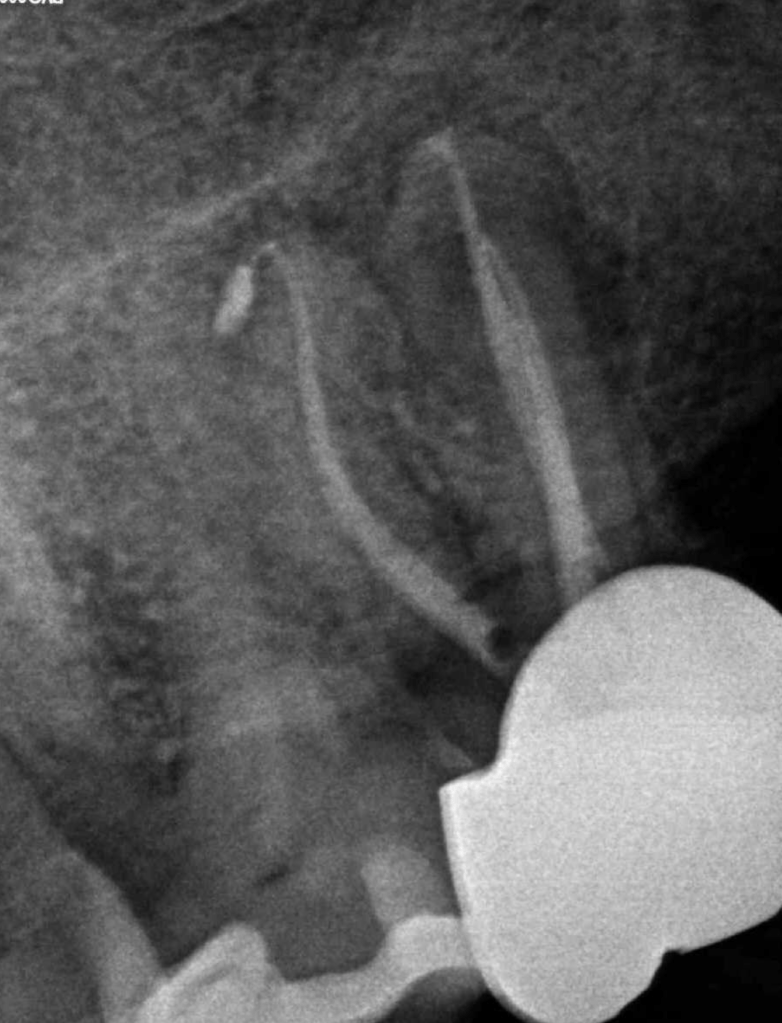

Retratamiento, conducto distal